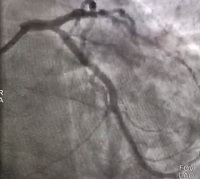

В центре началась запись на коронарографию и другие виды интервенций

В сотрудничестве с коллективом интервенционных кардиологов под руководством Главного внештатного специалиста МЗ РФ по рентгенэндоваскулярным диагностике и лечению в Северо-Западном федеральном...

Слаженная работа центра помогла оказать экстренную помощь

Слаженная работа сотрудников центра, а также врачей неотложной помощи и рентгенохирургов Всеволожской КМБ помогла справиться с экстренной ситуацией. 02.02.2022 мужчина 60 лет обратился в наш центр в...

02.02.2022 22:20